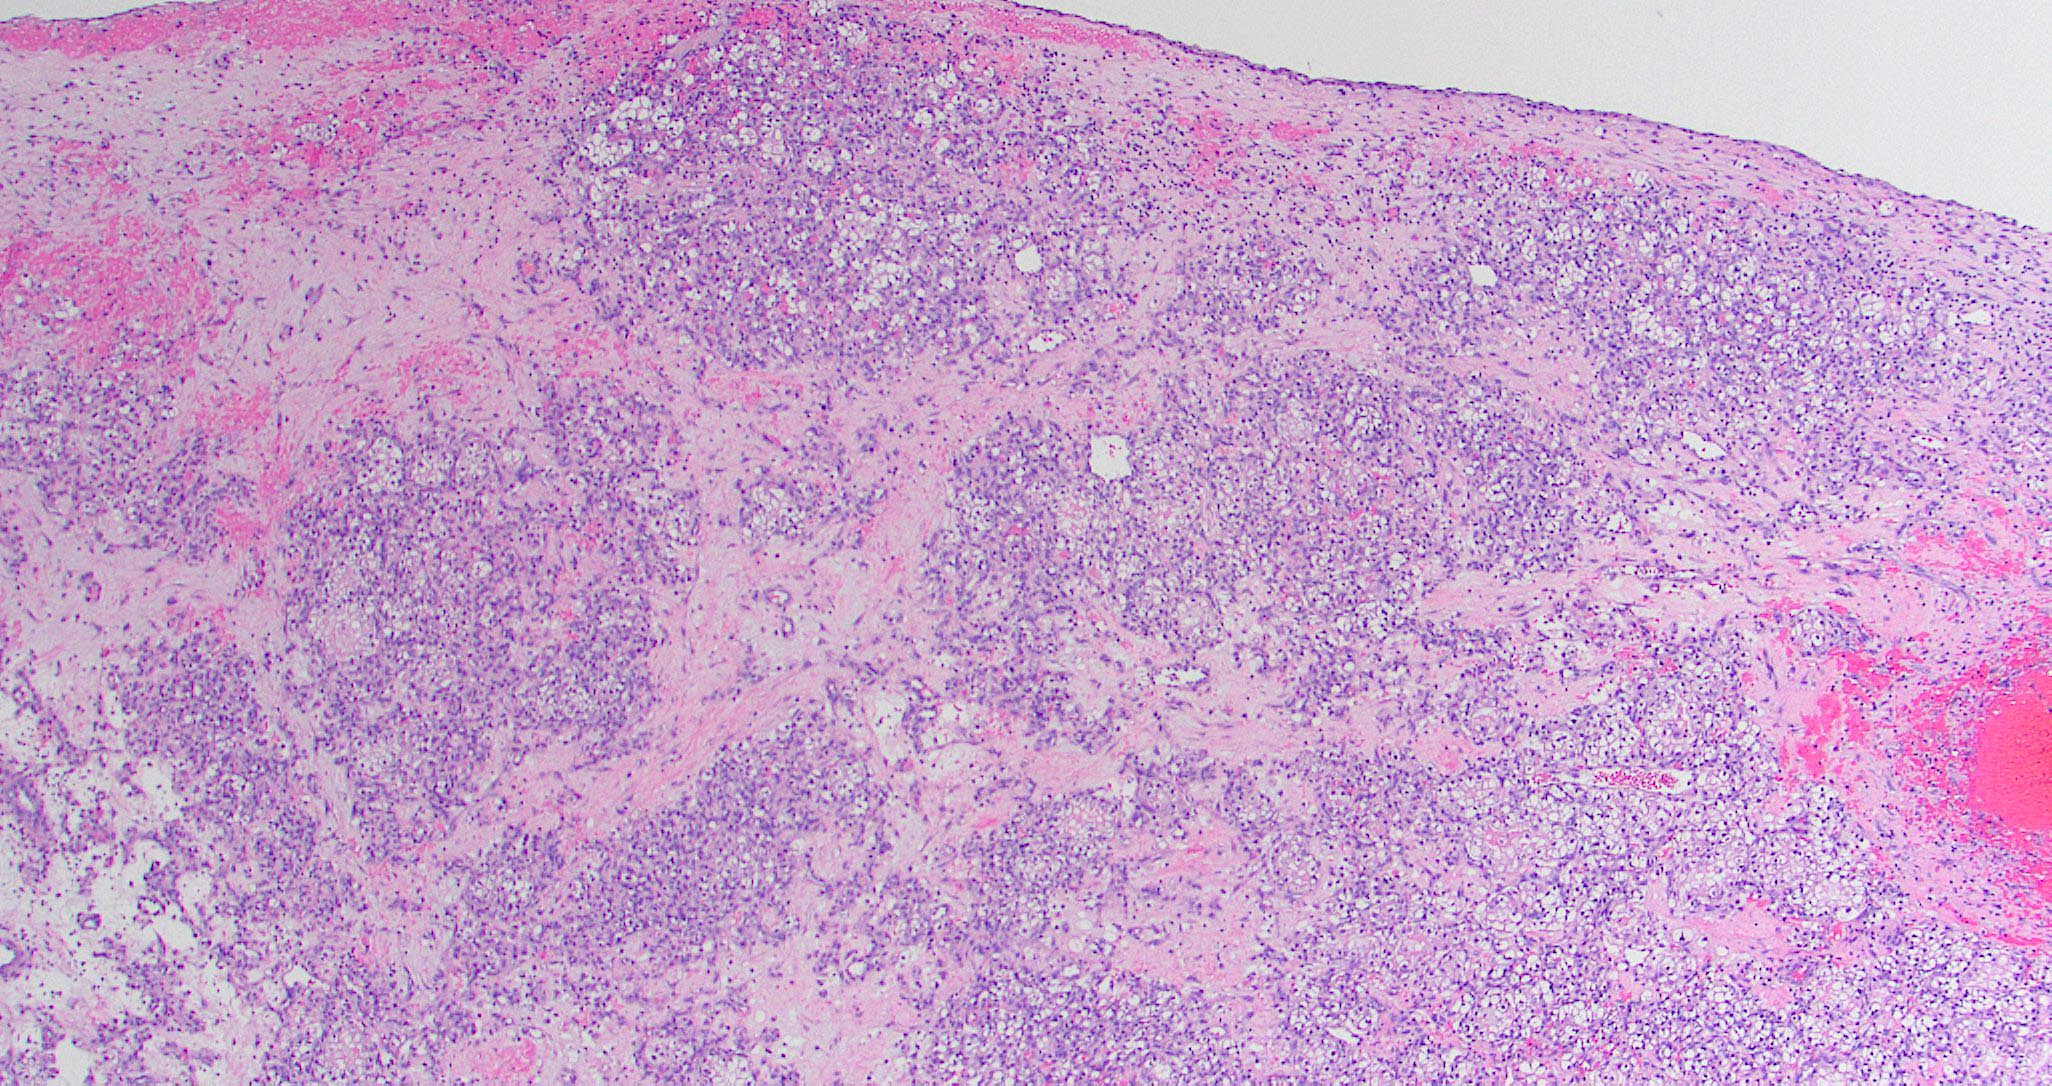

Microscopic (histologic) images

Contributed by Diana Bell, M.D.

Sinonasal renal cell-like adenocarcinoma

- Sinonasal renal cell-like adenocarcinoma (SRCLA) is a recently described (first case in 2002) subtype of low grade non-ITAC

- SRCLA exhibits uniform, cuboidal to polyhedral glycogen rich cells with clear cytoplasm that lacks mucin production (Head Neck Pathol 2016;10:68)